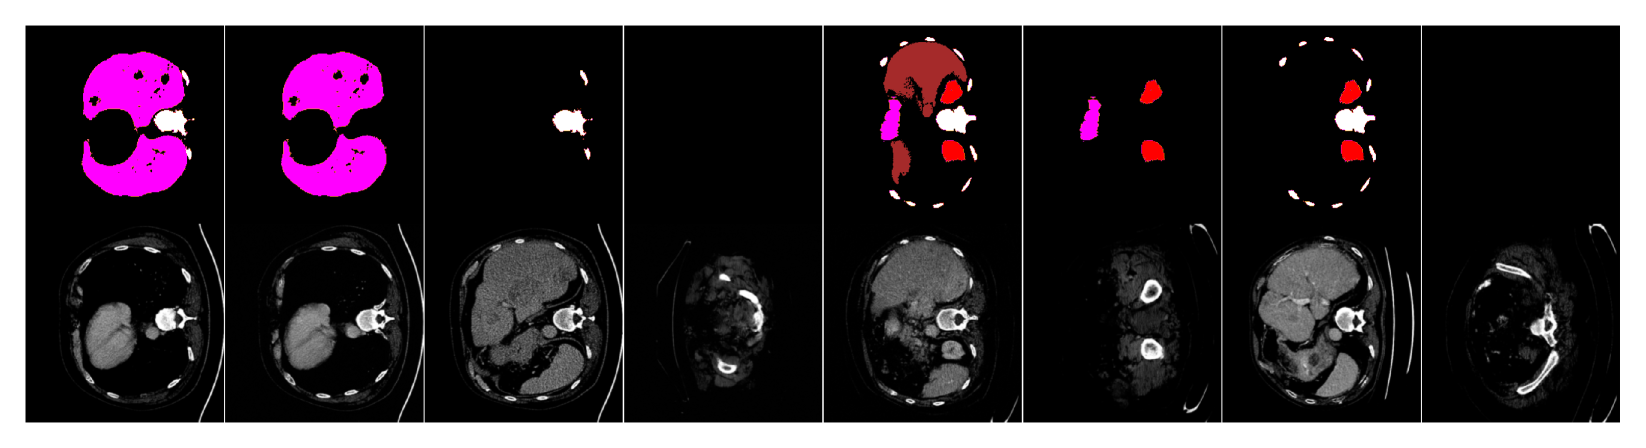

We will now compare our segmentation-guided diffusion model (“Seg-Diff” for short) to various state-of-the-art image generation models trained on each dataset: (1) the segmentation-conditional model ControlNet [Zhang et al.(2023)Zhang, Rao, and Agrawala], and the unconditional models of (2) a diffusion model identical to ours but trained without mask conditioning, and (3) StyleGAN2-ADA [Karras et al.(2020)Karras, Aittala, Hellsten, Laine, Lehtinen, and Aila], a state-of-the-art GAN model. We abbreviate these as CtrlNet, Unc-Diff and GAN, respectively, and training details for each are in Appendix A.2. We show exemplar generated images from all models in Fig. LABEL:fig:samples (more in Appendix D); for conditional models, input masks were randomly sampled from the test set.

fig:samples

We first attempted to use the common Fréchet Inception Distance (FID) [Heusel et al.(2017)Heusel, Ramsauer, Unterthiner, Nessler, and Hochreiter] as a metric for generated image quality/realism compared to real data. Since the original FID utilizes a CNN image encoder pre-trained on natural images, which may fail to capture the characteristics of medical images, we propose to instead use an encoder trained on the corresponding medical image dataset. We observe that samples generated from both the segmentation-guided and unconditional diffusion models achieve promising results, (e.g., for breast MRI), yet the CNN-based FID fails to capture the global feature of anatomical realism that can differ in images generated by these models (e.g., fibroglandular tissue as shown in Fig. LABEL:fig:eg_imgs).